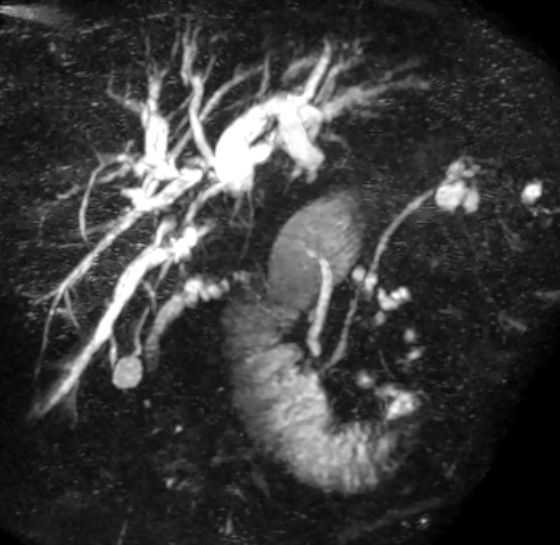

| Diagnostik | 80-jähriger Mann mit Verschlussikterus. Die MRCP zeigt eine Erweiterung der intrahepatischen Gallenwege und einen Gangabbruch im Bereich des Leberhilus. ![]() | |||